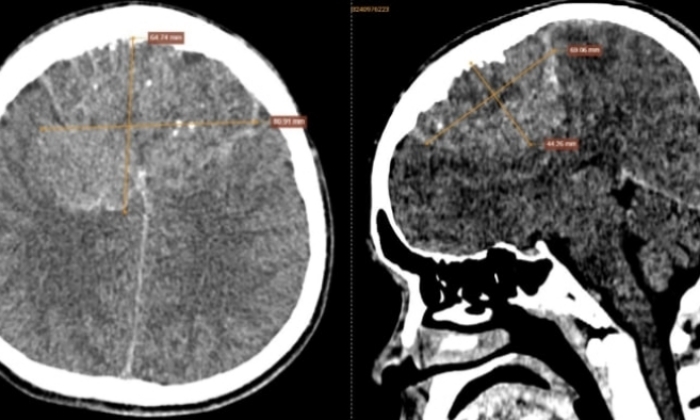

Sau khi đi khám tại cơ sở y tế địa phương, anh được chỉ định chụp CT sọ não không tiêm thuốc cản quang. Kết quả chụp cho thấy một khối bất thường vùng trán sát bản xương sọ, có dạng mô mềm, bờ không đều, ranh giới rõ ràng nhưng kèm phù não nhẹ. Bên trong khối u xuất hiện nhiều nốt vôi hóa và ổ hoại tử, kích thước lên tới 80 x 65 x 55 mm.

Hình ảnh chụp cắt lớp vi tính sọ não không tiêm thuốc cản quang của bệnh nhân phát hiện tổn thương.